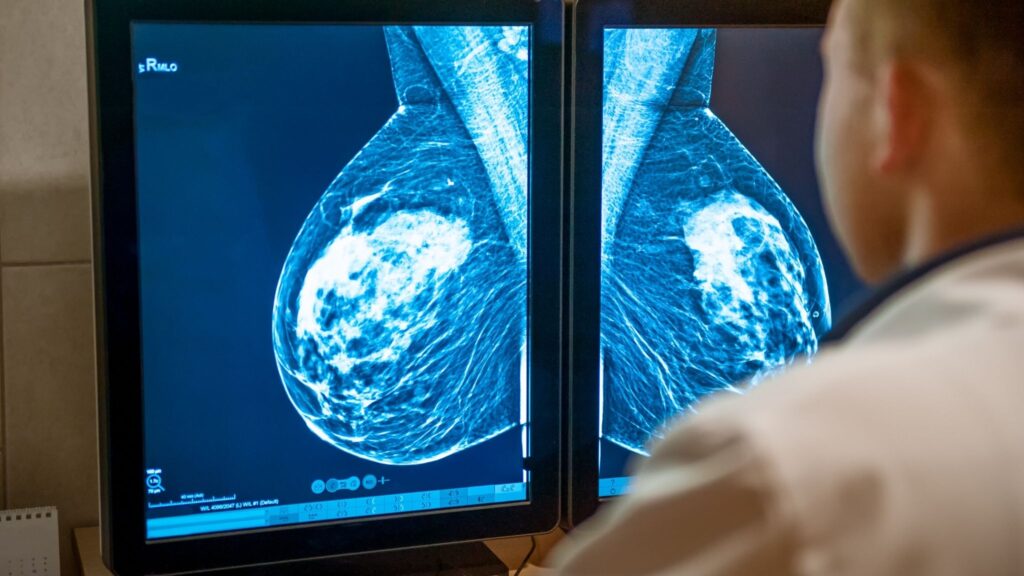

O avanço da medicina preventiva tem permitido que mulheres vivam mais e com maior qualidade de vida, o que levanta a questão: até que idade a mamografia continua sendo útil?

Tradicionalmente recomendada entre os 50 e 70 anos, uma nova pesquisa indica que mulheres com mais de 80 anos podem se beneficiar significativamente do rastreamento, desde que estejam em bom estado de saúde e tenham expectativa de vida prolongada.

Um estudo recente publicado no Annals of Surgical Oncology analisou 174 mulheres com mais de 80 anos diagnosticadas com câncer de mama entre 2013 e 2020. As mulheres participantes do estudo foram divididas em dois grupos: aquelas que realizaram mamografia nos últimos dois anos e aquelas que não realizaram. Os resultados mostraram:

• Tumores menores e menos agressivos entre as mulheres rastreadas

• Tratamentos menos invasivos, com menor necessidade de quimioterapia, radioterapia ou biópsia de linfonodo

• 55% menos risco de recorrência do câncer

• Redução de 74% no risco de morte

Esses dados reforçam que a detecção precoce tem impacto direto na sobrevida e na qualidade de vida, permitindo intervenções mais seguras e menos traumáticas.